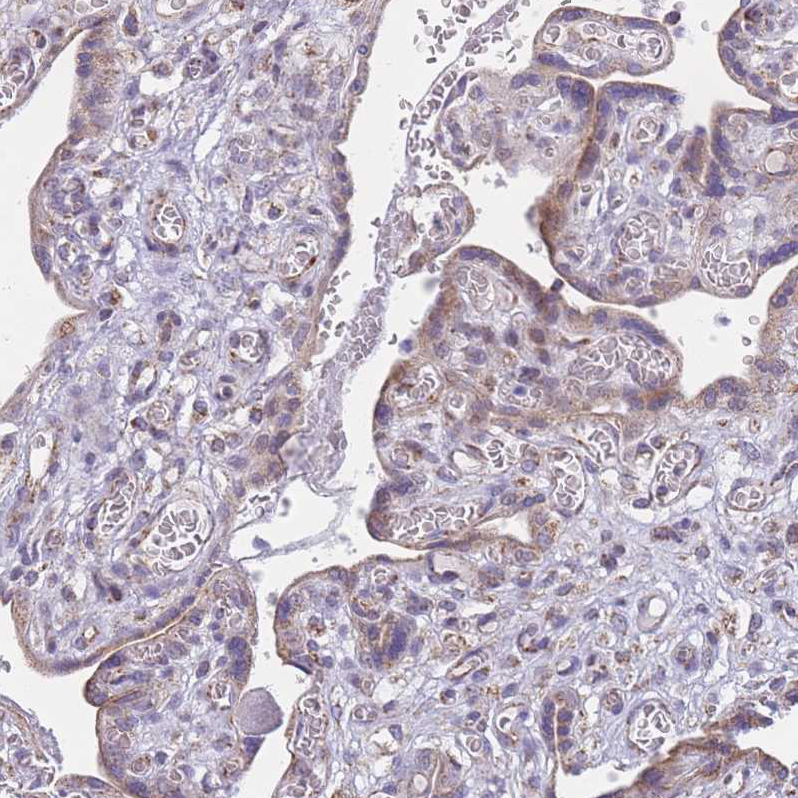

Immunohistochemical staining of human testis shows moderate to strong granular cytoplasmic positivity in Leydig cells.